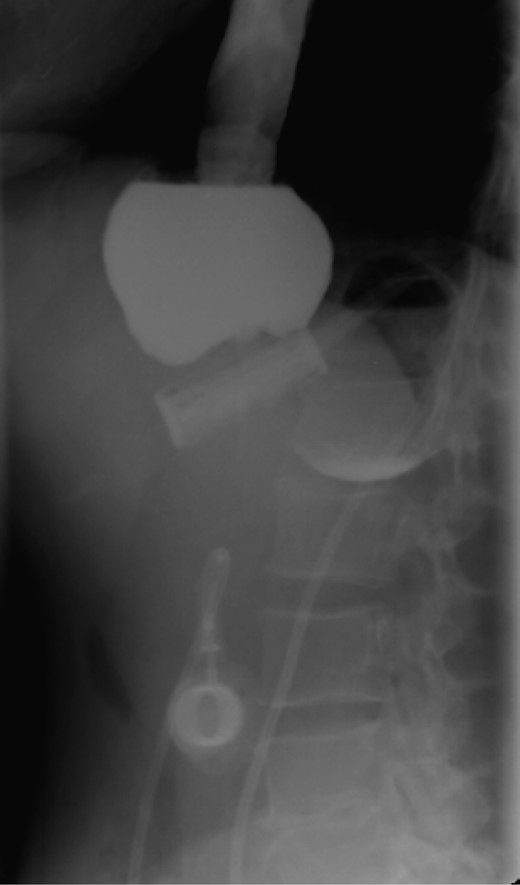

On the first day of admission, gastric banding was completely deflated. Rx abdomen showed posterior slippage of the ring (Fig. 1). Subsequently, the patient underwent rehydration therapy, 20-day total parenteral nutrition and infusion of human albumin. During that period, we examined her upper digestive tract with oral water-soluble contrast (Fig. 2) with the result of a thin liquid passage downstream of the ring and marked gastric pouch distension. Esofagogastroscopy was performed, which was negative for erosion or gastric perforation; however, it revealed a 1-cm-diameter passage through the gastric band. Despite an improvement in symptoms with partial resumption of semi-liquid intake, the patient continued to experience nausea and vomiting. For this reason, she underwent laparoscopic removal of gastric banding. In the operating room, she was placed in the lithotomy position; we placed a 10-mm optical trocar in supraumbilical region, a 5-mm one in the right upper quadrant and a 10-mm one in left upper quadrant near the subcutaneous tank. After lysis of adhesions between liver and stomach, the intraoperative picture showed a banding displacement, confirming posterior slippage of the banding and its sliding back to the level of previous gastro-jejunal anastomosis. Ascitic effusion due to dysproteinemia was reported. A methylene blue test showed no gastric perforation. After this procedure, the patient started to resume liquid intake in the first postoperative day and food intake in the second postoperative day, with complete resolution of vomiting and nausea. Then, she was discharged with the advice of an appropriate diet and invited to attend a recall visit 10 days later. In subsequent follow-up, the complete resolution of clinical symptoms was confirmed together with an improvement of the biohumoral picture.

Water-soluble contrast shows a thin liquid passage downstream of the ring and marked gastric pouch distension.